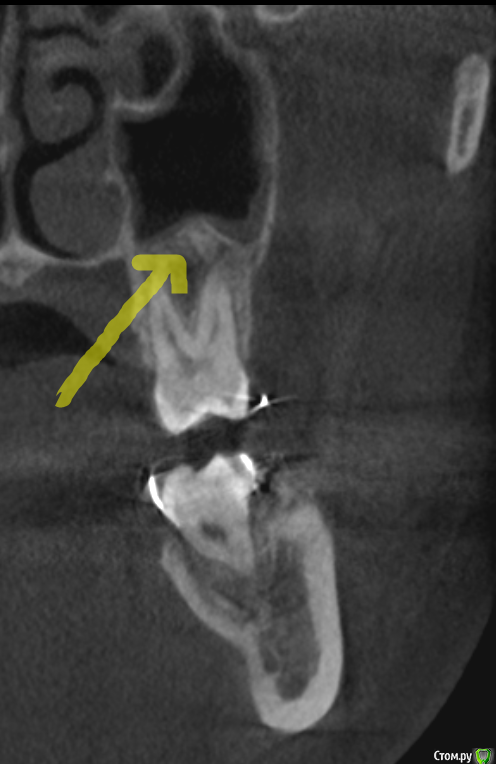

It'sGeorgy Опубликовано 30 ноября, 2019 Поделиться Опубликовано 30 ноября, 2019 Всем доброго времени суток! Пациентке в сторонней клиники 1.5 года назад удаляли 2.8 зуб. Удаление заняло больше часа. После этого, с ее слов был гайморит, который пол года не могли вылечить т.к. не могли найти причину. На срезах(кт не могу прикрепить к сожалению сейчас):1 - Пазуха + сообщение2 - Состояние лунки3 - Недоудаленный корень в области 2.7 зуба(?) На слизистой ОАС не нашел. На данный момент активных жалоб нет, но порой "Побаливает". - Стоит ли лезть и пытаться закрывать сообщение? Какова методика операции и где можно про нее почитать?(До этого закрывал только ОАС с выходом на слизистую с помощью лоскута со щеки + ССТ) Или просто передать ЛОРу на удаление полипов из пазухи? - Стоит ли лезть и пытаться удалять корень или пусть там полежит? Ссылка на комментарий

It'sGeorgy Опубликовано 4 декабря, 2019 Автор Поделиться Опубликовано 4 декабря, 2019 тогда что Вы собрались закрывать???На КТ видно, что лунка не зарастает костной тканью из нее есть сообщение с пазухой. Прошло уже 1.5 года. Вопрос в том, нуждается ли это в лечении и где можно почитать про ведение таких случаев. Ссылка на комментарий

___49___ Опубликовано 4 декабря, 2019 Поделиться Опубликовано 4 декабря, 2019 (изменено) На КТ видно, что лунка не зарастает костной тканью из нее есть сообщение с пазухой. То , что костной ткани нет - видно. Не зарастает , но при этом нет ороонтрального сообщения - это как ? Если вы считаете, что наличие кости между полостью рта и пазухой обязательно , то это не так, недавно закрыл ороонтральное сообщение которому более 10 лет , при этом костный дефект(костное окно) между полостью рта и пазухой примерно 8 *8 мм. через 1.5 месяца ротоносовая проба отрицательна , пазуха чистая, костное окно без изменений и так скорее всего и останется , считаю пациентку выздоровевшей . В вашем случае наблюдал бы пациентку в динамике, показаний к травматичным операциям на данный момент нет , вероятность того, что апекс там проживет всю жизнь( так как полная ретенция вы писали и надеюсь без альвеолита ) и более не проявит себя, вполне имеет место быть . Изменено 4 декабря, 2019 пользователем ___49___ 2 Ссылка на комментарий

It'sGeorgy Опубликовано 13 декабря, 2019 Автор Поделиться Опубликовано 13 декабря, 2019 Повторно не нашёл открытого ОАС. Рото-носовая и носо-ротовые пробы отрицательны. Через пол года повторное КТ, буду смотреть на состояние пазухи и состояние лунки. Если хуже не станет, то, как написали выше, буду считать пациентку выздоровевшей. В прикреплениях - вероятное место лунки(не сравнивал ещё по КТ). 2 Ссылка на комментарий